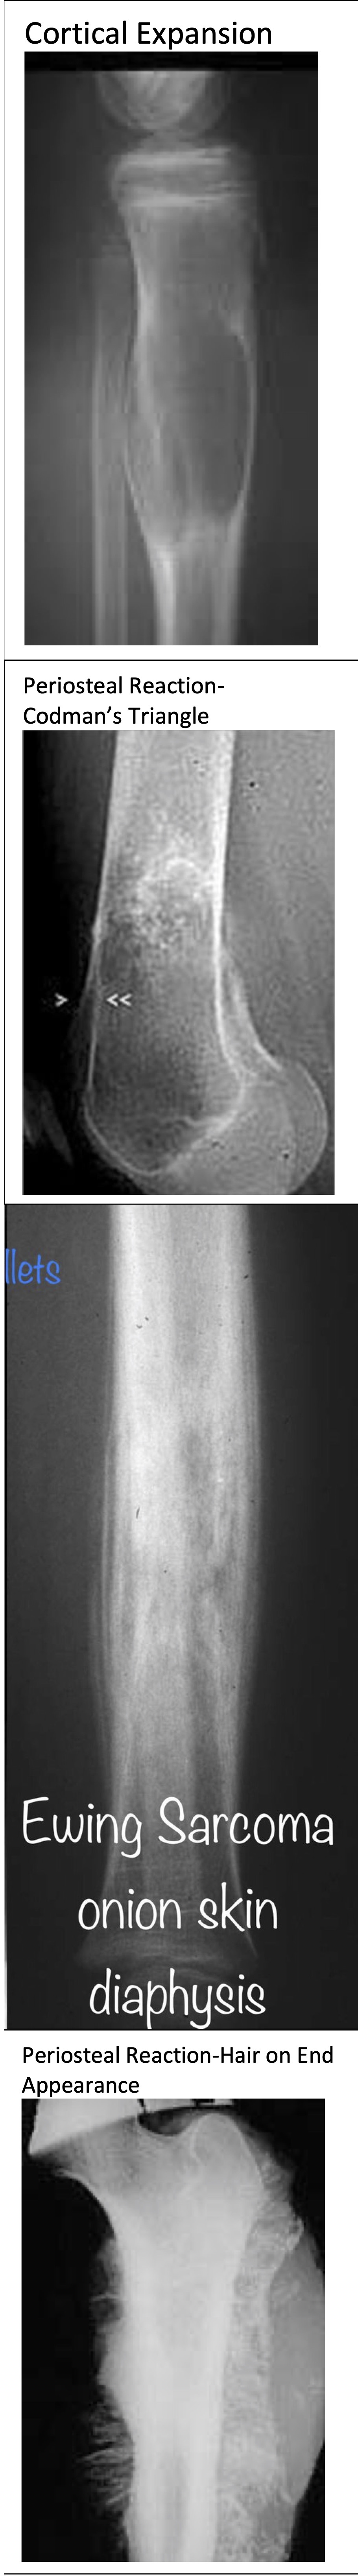

Periosteal Reactions

Rapidly Growing

Lesions